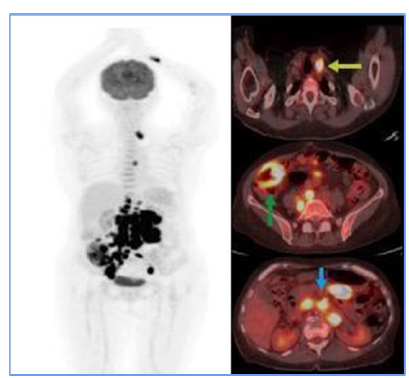

• July 22, 2021, PET-CT (F18-FDG): Supra- and infra-diaphragmatic hypermetabolic lymphadenopathies, suggesting glycolytic tumor activity; consideration of lymphoproliferative disease, diffuse thickening of the right ascending colon wall, and diffuse FDG uptake in the axial skeleton (Figure 1).

With these findings and the relevant clinical analysis, the diagnosis of IDCS was considered at the time, and treatment was initiated. The patient underwent 6 sessions of R-CHOP chemotherapy. Flow cytometry in the bone marrow showed aberrant plasma cells at 0.11%, and a PET-CT (F18-FDG), when compared to the initial study, reported resolution of supra- and infra-diaphragmatic adenopathy (See Figure 1). The scan also showed an iliac internal chain adenopathy with FDG uptake, surpassing liver uptake, which, based on Deauville criteria, scored a 4, thus indicating a partial response to treatment.

Figure 1

Initial PET CT. Hypermetabolic supra (yellow arrow) and infra diaphragmatic (blue arrow) adenopathy suggest tumor glycolytic activity. Diffuse mural thickening of the hypermetabolic ascending colon (green arrow) in the clinical context of suspected lymphoproliferative disease suggests extranodal involvement.

For staging, PET-CT (F18-FDG) is a crucial tool. Initially, it allowed for documentation of both nodal and extranodal involvement, establishing tumor viability and aiding in follow-up and evaluation of treatment response. The Deauville 5-point visual scale [7] was used to assess treatment response. In this case, the PET-CT documented persistent disease (Deauville 4), which influenced treatment decisions and led to escalation of the medical management. A subsequent PET-CT (F18-FDG) performed after rescue therapy demonstrated a complete metabolic response at the end of treatment [8].

In the case presented here, the patient showed a favorable response to chemotherapy, achieving complete remission and surviving for two years to date. Lymph node and extranodal involvement, along with immunohistochemical findings, enabled the diagnosis and timely treatment initiation (Figure 1). The partial metabolic response observed in the post-treatment PET (Figure 2) led to the decision to escalate the treatment to second-line RICE chemotherapy. Eventually, a new PET-CT (F18-FDG) post-treatment (Figure 3) confirmed a complete metabolic response.